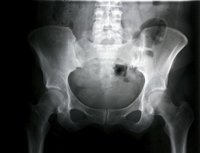

La realización de un programa de ejercicios en casa para los pacientes que completaron la rehabilitación estándar tras una fractura de cadera mejora la función física, según los resultados de un estudio que se publican este miércoles en la revista 'JAMA'. El tratamiento en el hogar consiste en realizar ejercicios como ponerse de pie desde la posición de sentado en una silla o subir un escalón.

Más de 250.000 personas en Estados Unidos se fracturan la cadera cada año y muchos de experimentan consecuencias graves a largo plazo. "Dos años después de una fractura de cadera, más de la mitad de los hombres y el 39 por ciento de las mujeres han fallecido o viven en un centro de cuidados a largo plazo. Muchos de ellos ya no son capaces de realizar tareas funcionales básicas completas independientemente de que pudieran llevarlas a cabo antes de la la fractura, como dar la vuelta a la manzana o subir cinco escalones dos años después de una fractura", según la información de respaldo del artículo.

La directora de este estudio, Nancy K. Latham, de la Universidad de Boston, en Estados Unidos, y sus colegas asignaron al azar a 232 adultos mayores funcionalmente limitados que habían completado la rehabilitación tradicional después de una fractura de cadera a un programa de ejercicios de cadera en casa que comprende algunos de orientación funcional (como ponerse de pie desde una silla o subir un escalón) impartido por un fisioterapeuta y realizado de forma independiente por los participantes en sus casas durante seis meses (120 participantes) o educación sobre nutrición cardiovascular en casa y por teléfono (112).